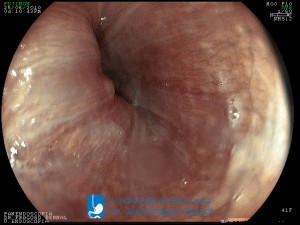

La Unidad de Endoscopía fue creada en 2002 por el Dr. Jesús Fragoso Bernal, es pionera en el estado por la utilización de la tecnología más avanzada, que nos permite ofrecer servicios integrales de diagnóstico y tratamiento para las enfermedades del aparato digestivo.

El profesionalismo de nuestro personal, altamente especializado, se distingue por la calidad y calidez de nuestros servicios con el objetivo de brindar una atención de excelencia en el ambiente más confortable para comodidad y seguridad de nuestros pacientes.

"La Unidad de Endoscopía se ha caracterizado por un progreso continuo desde su inicio marcando la pauta en los procedimientos endoscópicos en el estado de Tlaxcala y estando siempre a la vanguardia tecnológica."

Dr. Jesús Fragoso Bernal